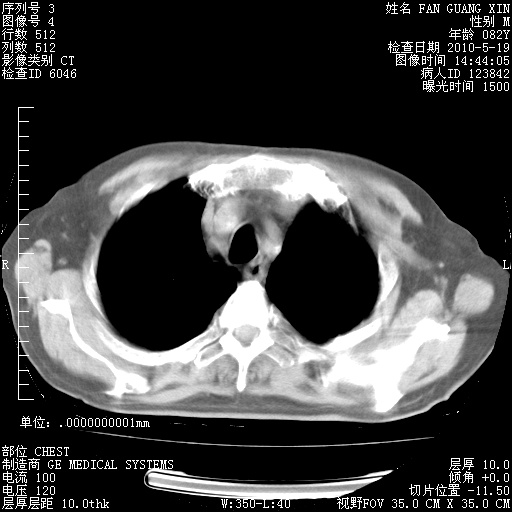

复查肺部CT,明显好转。为什么发热呢?

治疗3周后的肺部CT

治疗3周后的肺部CT纵隔窗